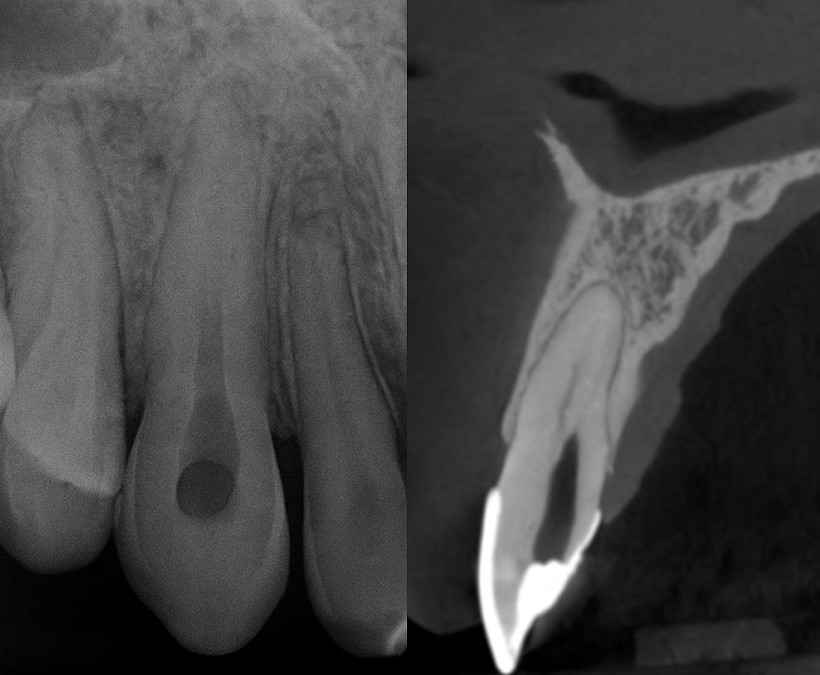

Casos Clínicos

Casos reais de acesso a canais calcificados, remoção de pinos com as Brocas através da Endodontia Guiada de Precisão. Veja as etapas, imagens, documentação e resultados obtidos em diversas situações.

Vídeos de casos reais